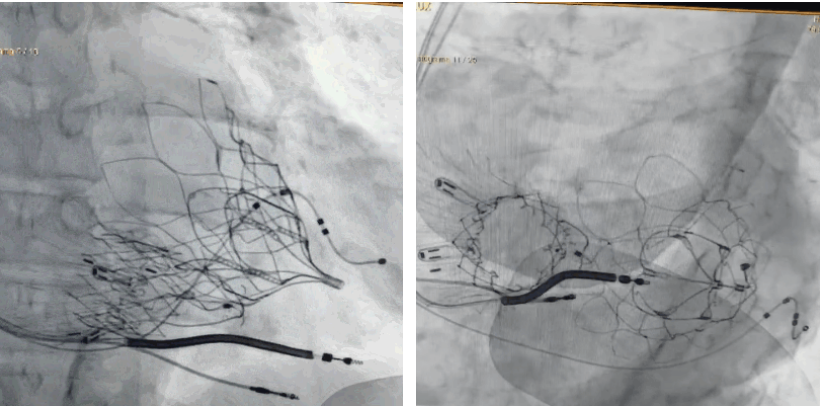

術(shù)后DSA顯示Lux-Valve Plus與Tendyne和ICD無相互影響

手術(shù)在全麻狀態(tài)下進(jìn)行。術(shù)者采用經(jīng)右側(cè)頸靜脈入路的方式將輸送器送入患者心臟內(nèi),在TEE及DSA引導(dǎo)下調(diào)整輸送器頭端角度,使得輸送器與三尖瓣瓣環(huán)平面垂直。在輸送器進(jìn)入右心室后釋放室間隔錨定裝置,而后釋放瓣葉夾持件(2個耳片結(jié)構(gòu))成垂直狀態(tài)。在TEE及DSA確定夾持件固定至三尖瓣葉根部且位于右室側(cè)后釋放人工瓣心房側(cè)盤片。隨后調(diào)整瓣膜同軸性以及室間隔錨定件位置(貼合室間隔),前推藏針管并固定,進(jìn)而釋放室間隔錨定裝置,并再次確認(rèn)瓣膜位置、穩(wěn)定性及同軸性,合攏輸送鞘后撤出輸送器,完成LuX-Valve Plus人工三尖瓣瓣膜的植入,僅殘余微量瓣周漏。且經(jīng)手術(shù)中心電生理團(tuán)隊評估,病人的起搏器和ICD功能沒有受到影響。